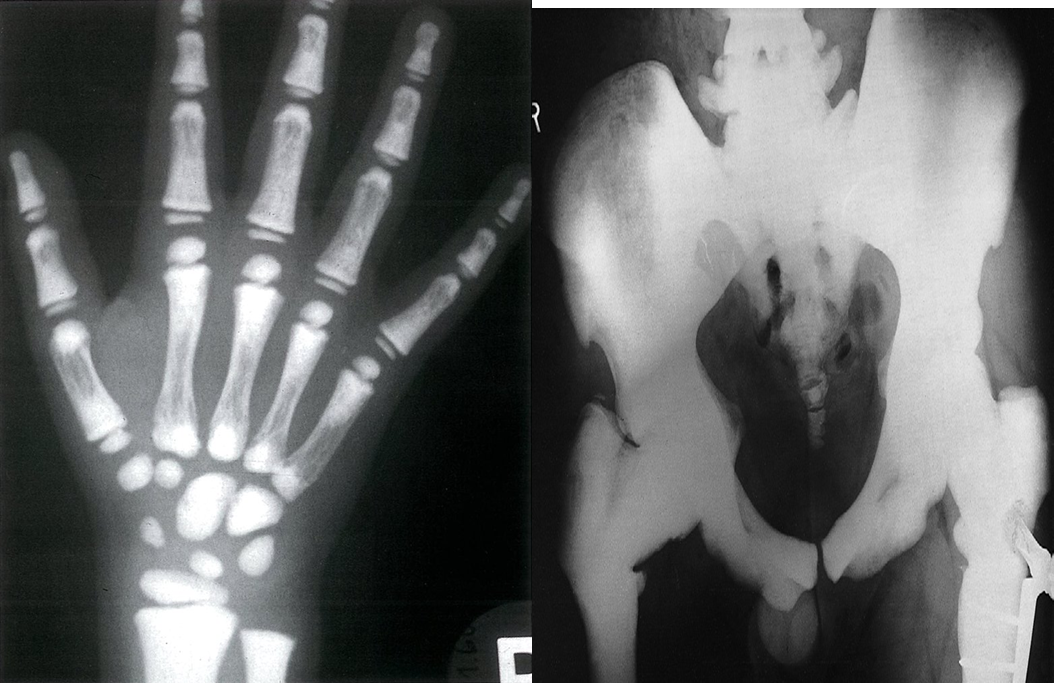

Anteroposterior x-ray of the hand of an 8-year-old girl: pronounced metaphyseal densities in line with increased sclerotization of the bones of the fingers.

There is a marked generalized increased bone density affecting all bones. There are multiple healed fractures, with a pin and plate in the left femur.